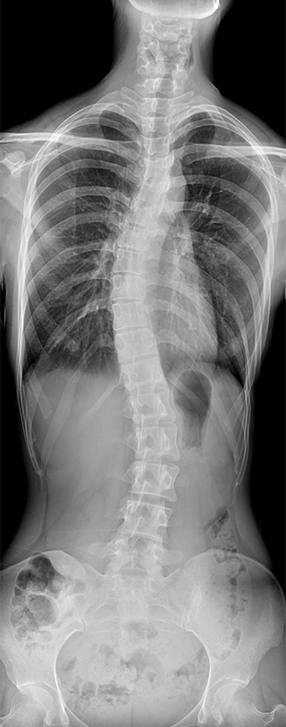

• 拍片

适用于全身各部位摄影

(常规摄影和特殊摄影)

临床图像